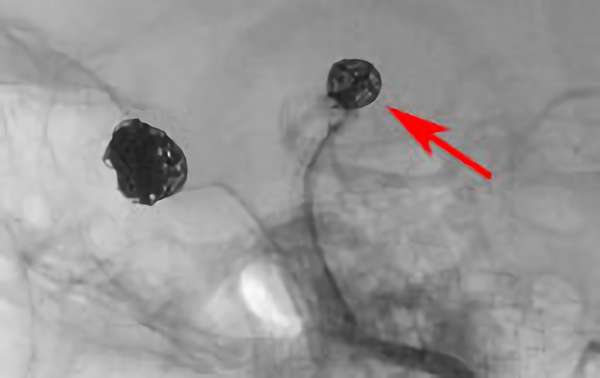

No.1617 手術中